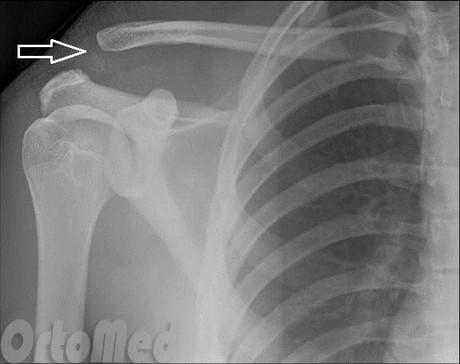

Для подстверждения диагноза выполняется рентгенография плечевого сустава. На рентгенограмме четко видно, если произошел вывих акромиального конца ключицы.

Диагноз вывиха акромиального конца ключицы

Диагноз вывиха акромиального конца ключицы иногда очень прост и все очевидно при осмотре, а иногда приходится решать целую головоломку. Наиболее оптимальным и распространенным способом диагностики является рентгенография. Стоит сказать, что, как не бывает одинаковых людей, так и не бывает одинаковых ключиц. Чаще всего причиной ложного диагноза индивидуальные особенности акромиально-ключичного сустава.

Поэтому целесообразно выполнять рентгенограмму не одного плеча, а двух сразу - что позволит оценить нормальное строение противоположной ключицы.

В сомнительных случаях иногда выполняют функциональную рентгенографию - в руку берут груз, который оттягивает ее вниз и вывих становится более очевидным.